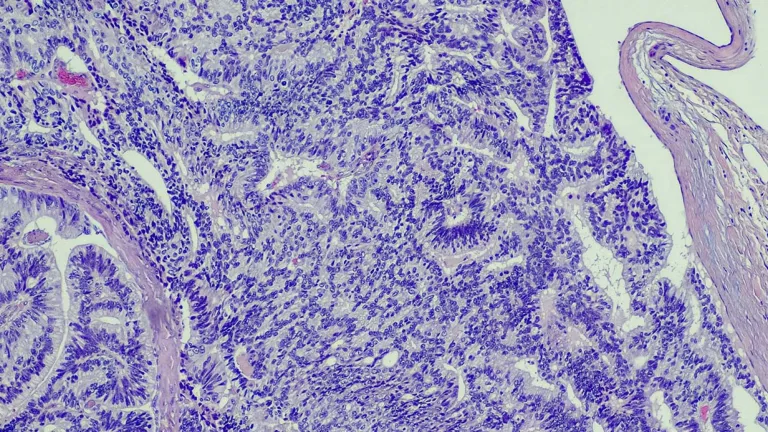

Pathologists

Cornelia Ding, MD, PhD

- Assistant Professor of Pathology and Urology